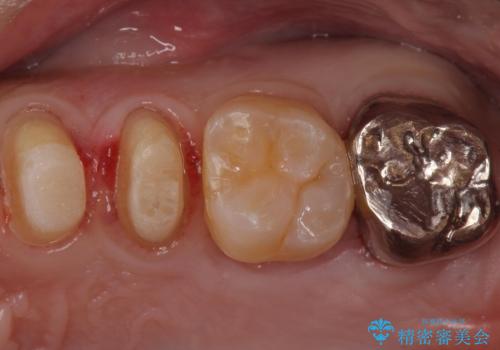

奥歯は十分な歯の高さがなかったため、クラウンをかぶせる前に歯周外科治療で歯の高さを出しています。

歯科に通うようになってから磨き残しの状態も改善されていきました。